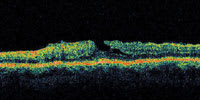

| Figure 3. This patient has vision of 20/30, but has an early apparent peeling of the inner retina along one side of the fovea. This may represent a laterally ruptured cyst and may or may not represent an early macular hole formation. |

A central clinical challenge has been accurately diagnosing early macular holes which may be mimicked by many other conditions.34,35 No imaging modality has enhanced our diagnostic capability more than the OCT; superior imaging capabilities have improved diagnostic accuracy, clinical monitoring, and postoperative assessment.36-38 The OCT unequivocally demonstrates early stages of full-thickness macular holes (Figure 1), and allows distinction of pseudohole and pre-macular hole conditions in almost all instances. Fluid accumulation in early, presumed pre-macular hole stages have been corroborated by OCT observations (Figure 2). Serial images have been reported showing the progression from apparent impending macular holes to full thickness macular holes.39-42 It has depicted many other configurations that might be in the spectrum of lamellar or pre-macular hole conditions (Figure 3 and 4).

Regardless of the initiating mechanism, once the vitreous separates, an early (occult) macular hole could repair itself (especially if very small) via glial proliferation with little or no clinical symptoms or signs. If a full-thickness macular hole first presents as reopening of a previously undetected, self-healed macular hole, this could account for the predominance of (hyperplastic) Mueller cells and glial cells found in the removed opercula. If the discontinuity is too large, migration of reparative, proliferating glial cells is impeded,57 so a macular hole would enlarge as the glial cells which migrated around the hole edge onto the perifoveal internal limiting membrane progressively contract. The hydration theory is a novel concept that describes a mechanism by which a tiny dehiscence might permit increasing degrees of perifoveal cystic changes, and subsequently a dehiscence of a larger unit of inner retina (Figure 3).58